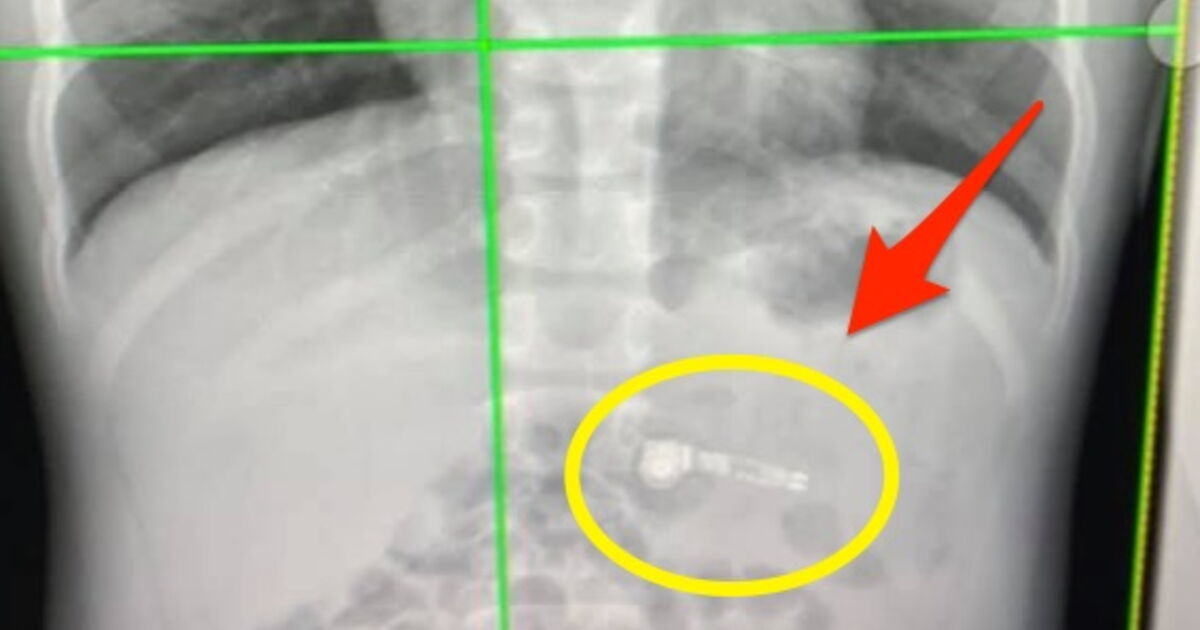

Man feels in chest, doctors find AirPod inside his body Can You Die From Swallowing An Airpod Because the human body is not meant to have a wireless listening device “wedged firmly” inside it, gauthier’s wife took. Well, as it turns out, the answer is probably yes. An airpods owner recently found out they had swallowed one of the earbuds after falling asleep while wearing them. It's one thing to accidentally swallow your airpod. If that can. Can You Die From Swallowing An Airpod.